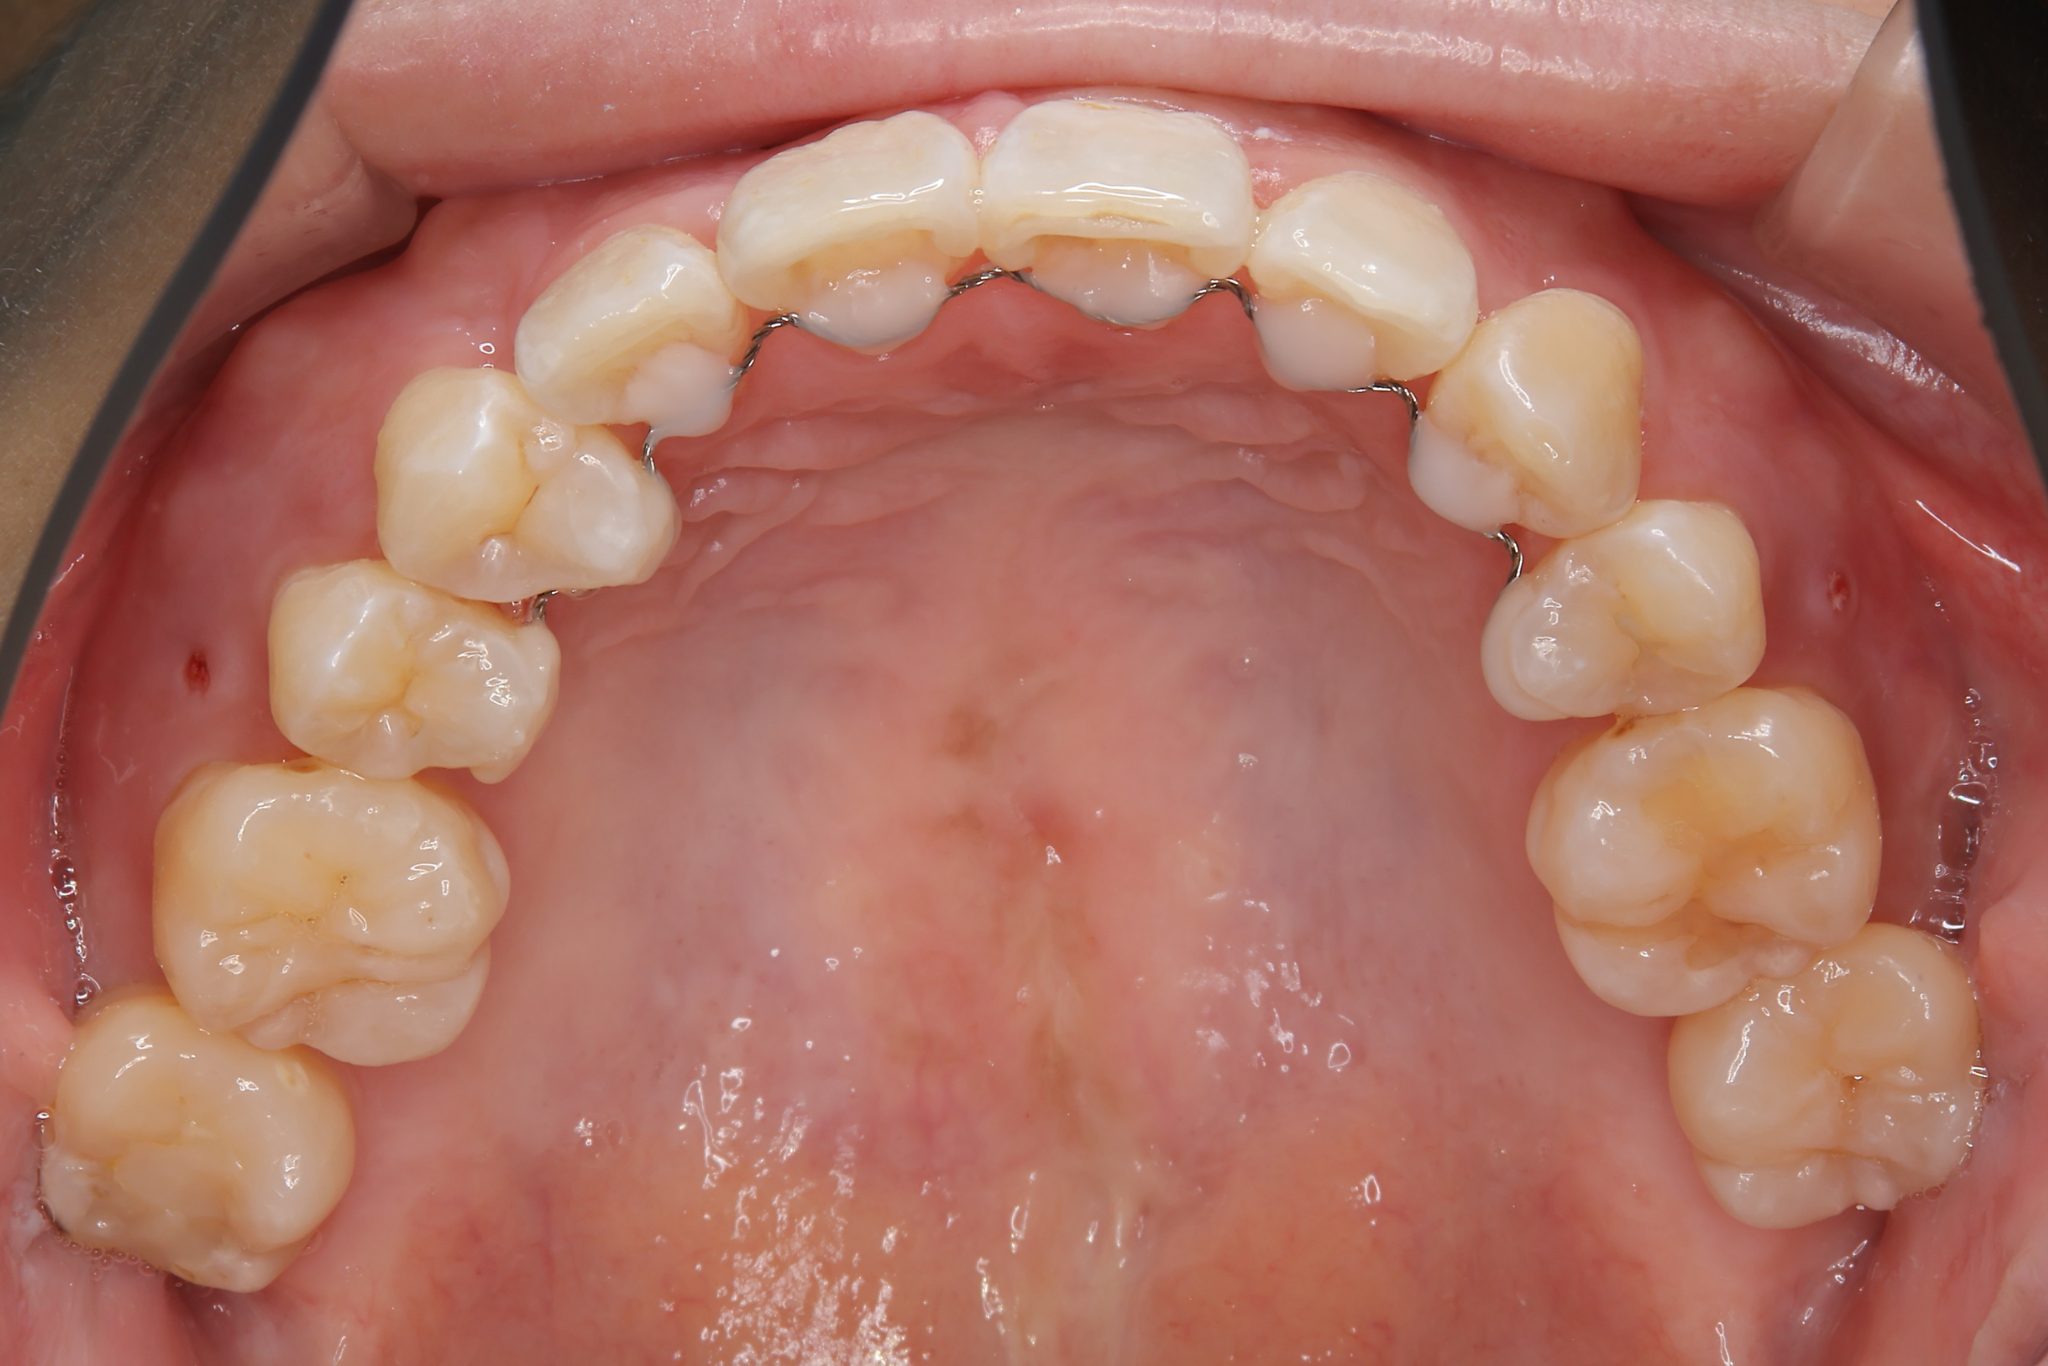

アフター

ワイヤー矯正治療|症例_814

施術内容 MSEと下顎リンガルアーチを用いて上下顎骨を拡大した。

その後上顎3・4番を抜歯しマルチブラケット装置とミニインプラントを用いて

歯牙を配列した。良好な咬合を獲得した。

治癒期間 1年8か月間